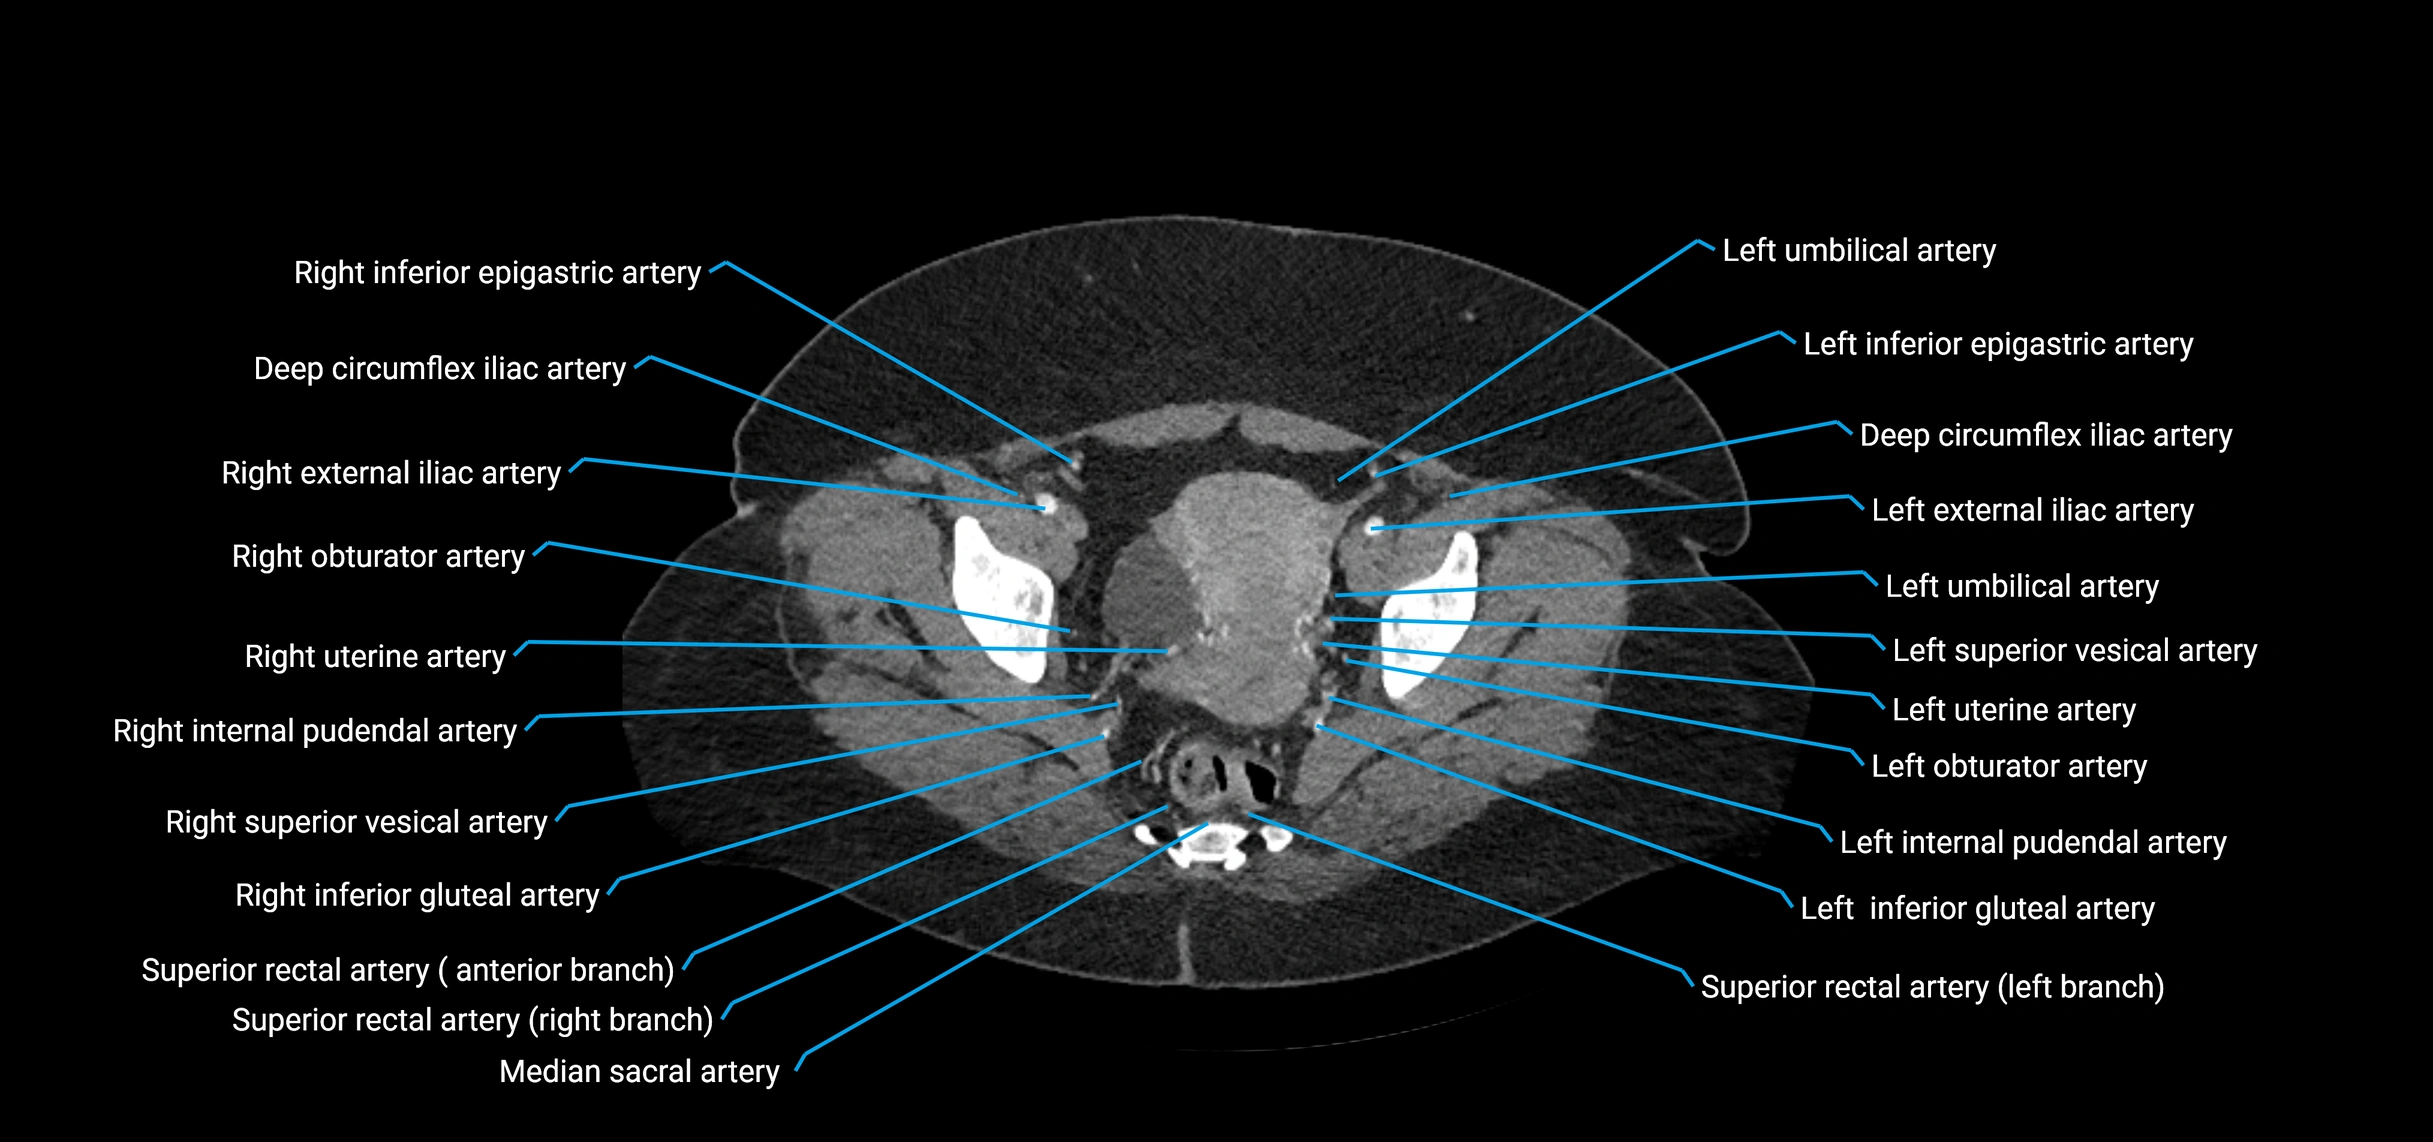

CT images

image

Contrast-enhanced CT (CTA):

• Gold standard for abdominal aortic imaging

• Provides excellent detail of lumen, wall, aneurysm, thrombus, and branch vessels

• Multiplanar and 3D reconstructions help in aneurysm measurement, stent graft planning, and dissection evaluation